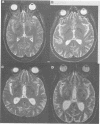

OBJECTIVES: To compare the results of clinical assessment and MRI with neuropathological findings in the diagnosis of HIV and cytomegalovirus (CMV) associated CNS disease. METHODS: A retrospective study of 35 patients infected with HIV who were examined at necropsy between four and 70 (median 20) days after neurological assessment and MRI. RESULTS: Of the 35 patients, 19 had diffuse white matter hyperintensity on T2 weighted MRI, six of whom also had focal lesions. Nine other patients had focal white matter lesions and seven had changes in cortical atrophy only. Necropsy in the 19 with diffuse white matter hyperintensity showed HIV leukoencephalopathy (HIVLEP) with encephalitis in 10, CMV encephalitis in three, both HIVLEP/HIV encephalitis and CMV encephalitis in one, lymphoma in three, and non-specific inflammation in two. Necropsy in the 16 other patients without diffuse white matter hyperintensity showed CMV encephalitis in six, HIV encephalitis (without HIVLEP) in two, CMV encephalitis and HIVLEP/HIV encephalitis in one, non-HIV associated abnormalities in five, herpes simplex encephalitis in one, and lymphoma in one. CMV DNA was detected in CSF of five of seven patients with CMV encephalitis and in two of two with CMV associated polyradiculopathy but without CMV encephalitis. Diffuse white matter hyperintensity on MRI had a sensitivity of 100%, a specificity of 66.6%, and a positive predictive value of 58% for diagnosis of HIVLEP. CONCLUSION: Diffuse white matter hyperintensity on MRI can be due to either HIV or CMV associated pathology or non-specific abnormalities.